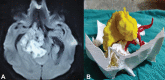

Three-dimensional (3D) printing technology in neurosurgery has gained popularity nowadays. Skull base contains many major neurovascular structures in a confined space, along with anatomical variations making surgical approaches to this region challenging. 3D-printed model of skull base tumors consists of the patient's bony skull base, actual tumor dimensions, and surrounding major neurovascular structures. We included a total number of five patients with skull base tumors (one case of planum sphenoidale meningioma, two cases of sellar tumor with suprasellar extension, and two cases of cerebellopontine angle tumor) and 3D-printed tumor model of each of them. These models were used for preoperative simulation and served as very true to life training tool. These help in increasing the efficacy of the surgeon, improves surgical safety and ergonomics. They were also used for patient counselling, educating about the disease, the surgical procedure, and associated risks.